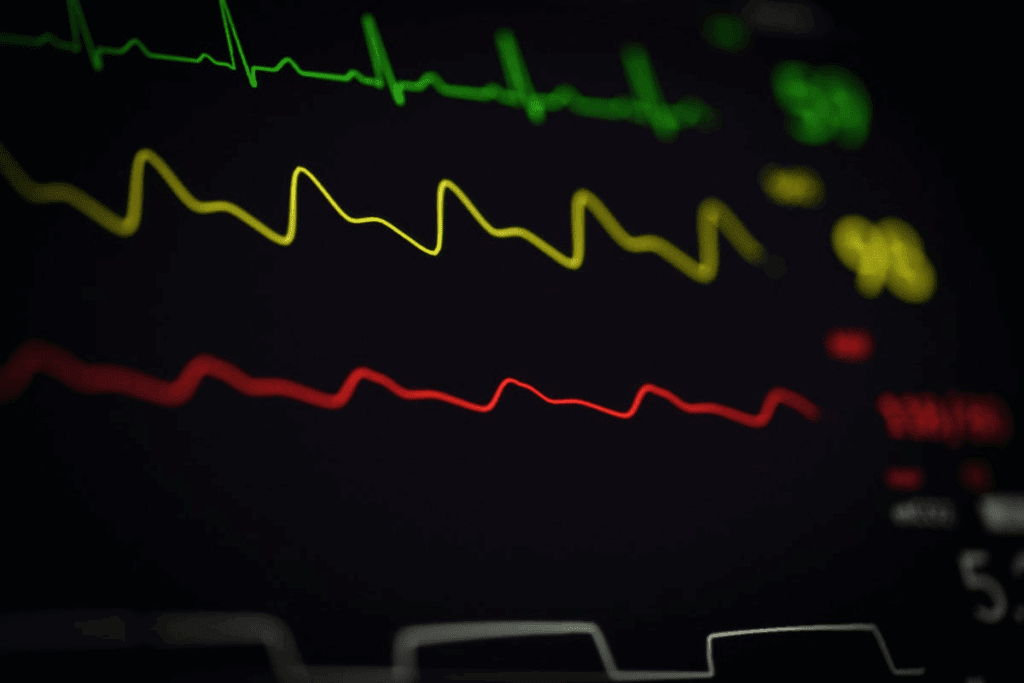

To diagnose third-degree AV block on an ECG, look for specific patterns. These patterns show that the atria and ventricles beat on their own.

Complete AV Dissociation

Complete AV dissociation is key to third-degree AV block. On an ECG, you’ll see:

- Regular P waves

- Regular QRS complexes

- No consistent relationship between P waves and QRS complexes

This means the electrical signals from the atria don’t reach the ventricles. This is because of a block in the AV node or further down.

Identifying P Waves and QRS Complexes

To spot AV dissociation on an ECG, we need to find the P waves and QRS complexes. P waves show when the atria depolarize. QRS complexes show when the ventricles depolarize. In third-degree AV block, these happen separately.

Looking closely at the ECG is key to spotting P waves. They might be hidden by QRS complexes or T waves. It’s also important to find QRS complexes and see if they’re conducted or escape beats.

Absence of Consistent PR Intervals

A key sign of AV dissociation is the lack of steady PR intervals. The PR interval is the time from the start of atrial depolarization (P wave) to the start of ventricular depolarization (QRS complex). In third-degree AV block, the PR intervals change randomly because the atria and ventricles don’t work together.

Usually, the atrial rate is higher than the ventricular rate. The PR intervals change without a pattern. This change is a main way to tell third-degree AV block apart from other heart block types.

Key Finding #5: Variable PR Intervals Without Pattern

Complete heart block is marked by PR intervals that change a lot and don’t follow a pattern. In third-degree AV block, the heart’s upper and lower chambers don’t work together well. This makes the PR intervals very unpredictable.

Looking at an ECG for third-degree AV block, measuring PR intervals is key. We see big changes in the time between P waves and QRS complexes. This shows a big problem with how the heart’s signals are sent.

Measuring PR Intervals in Complete Heart Block

To measure PR intervals, we look at when P waves start and QRS complexes begin. In complete heart block, these times are all over the place. This is because the heart’s upper and lower parts don’t work together.

Key Finding #6: Bradycardia in Third Degree Heart Block

Third-degree AV block often leads to bradycardia, a slow heart rate. This slow rate can affect the heart’s output and the patient’s health.

Typical Heart Rate Ranges

The heart rate in third-degree AV block is usually slow, often under 60 beats per minute (bpm). Sometimes, the rate can be even lower. For example, a junctional escape rhythm might keep the rate between 40-60 bpm. A ventricular escape rhythm can be slower, between 20-40 bpm.